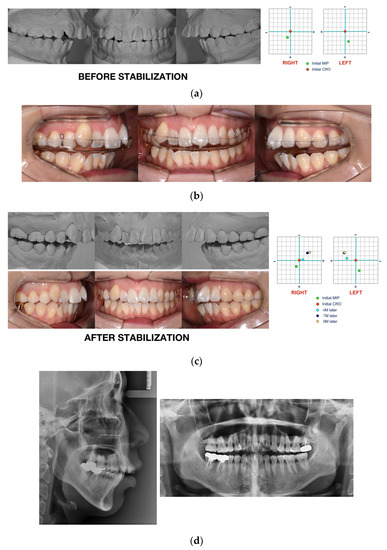

Case Report